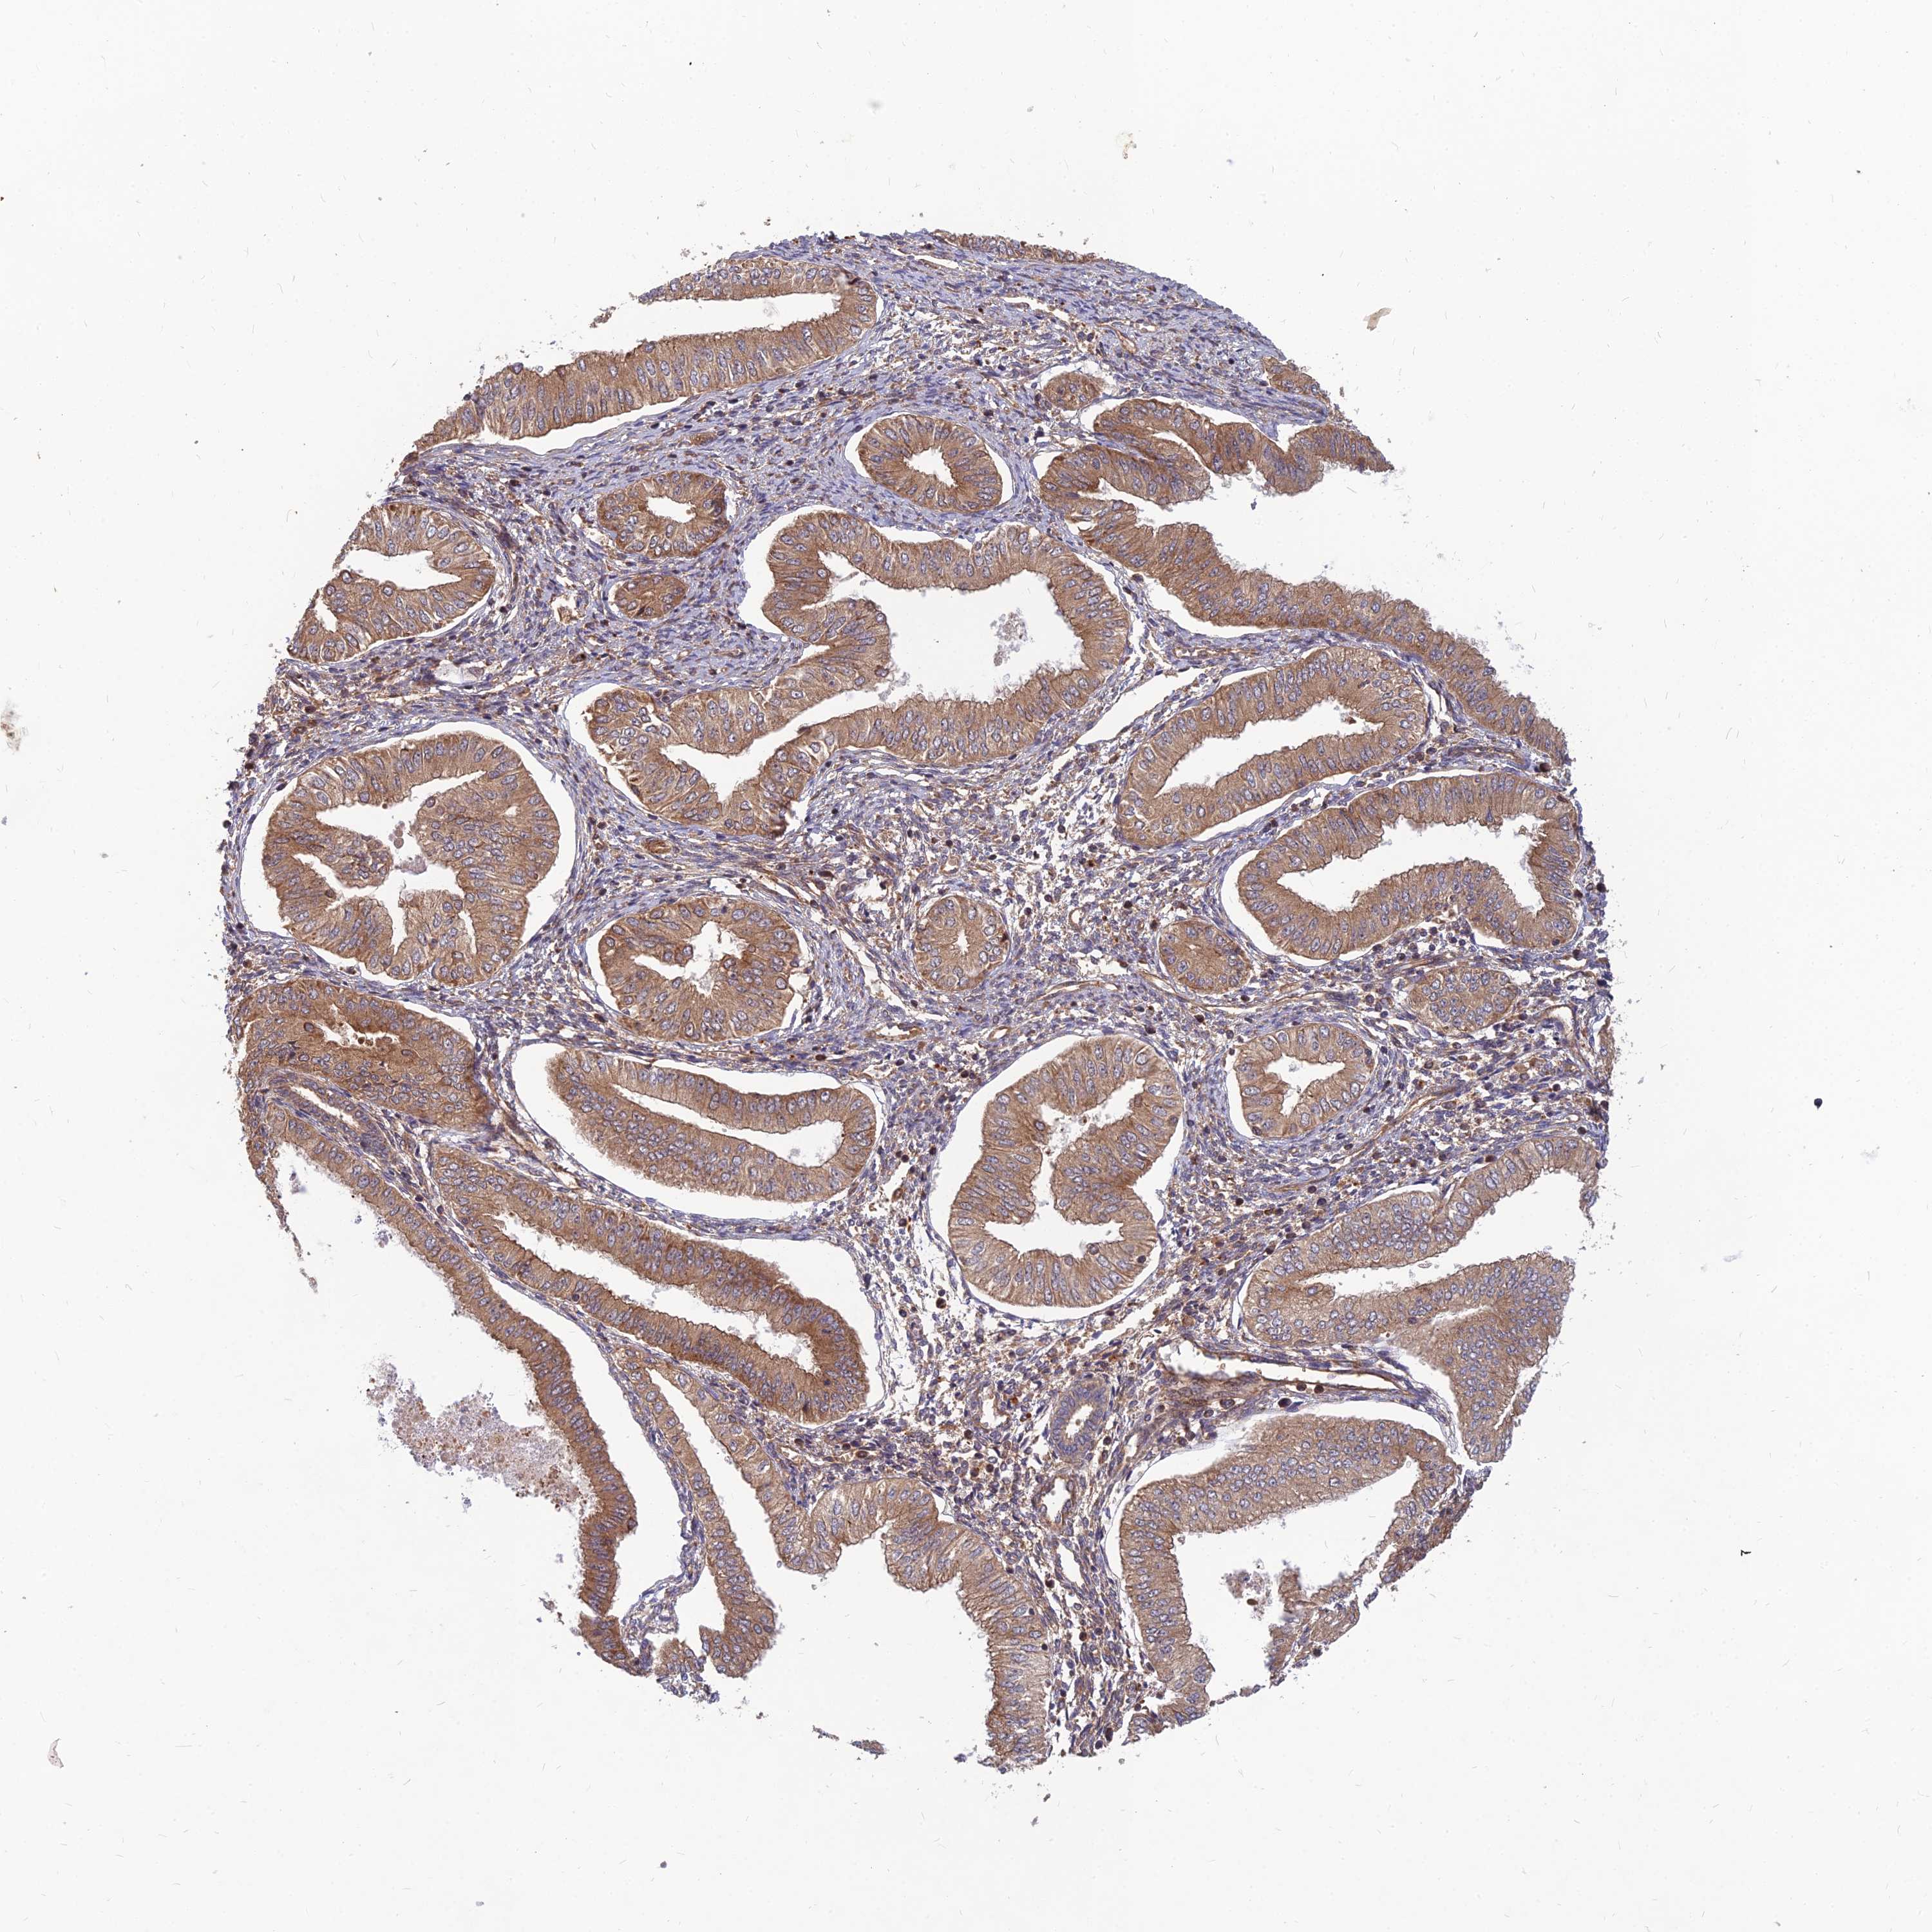

ENDOMETRIAL CANCER - Protein expressioni

A mouse-over function shows sample information and annotation data. Click on an image to view it in a full screen mode. Samples can be filtered based on level of antibody staining by selecting one or several of the following categories: high, medium, low and not detected. The assay and annotation is described here.

Note that samples used for immunohistochemistry by the Human Protein Atlas do not correspond to samples in the TCGA dataset.

Antibody stainingi

Antibody staining in the annotated cell types in the current human tissue is reported as not detected, low, medium, or high, based on conventional immunohistochemistry profiling in selected tissues. This score is based on the combination of the staining intensity and fraction of stained cells.

Each image is clickable and will lead to virtual microscopy that enables deeper exploration of all samples and also displays staining intensity scores, fraction scores and subcellular localization as well as patient and tissue information for each sample.

Antibody HPA039708

Antibody HPA040038

Staining

High

Medium

Low

Not detected

Intensity

Strong

Moderate

Weak

Negative

Quantity

>75%

75%-25%

<25%

None

Location

Nuclear

Cytoplasmic/membranous

Cytoplasmic/membranous,nuclear

Adenocarcinoma, NOS

Adenocarcinoma, metastatic, NOS